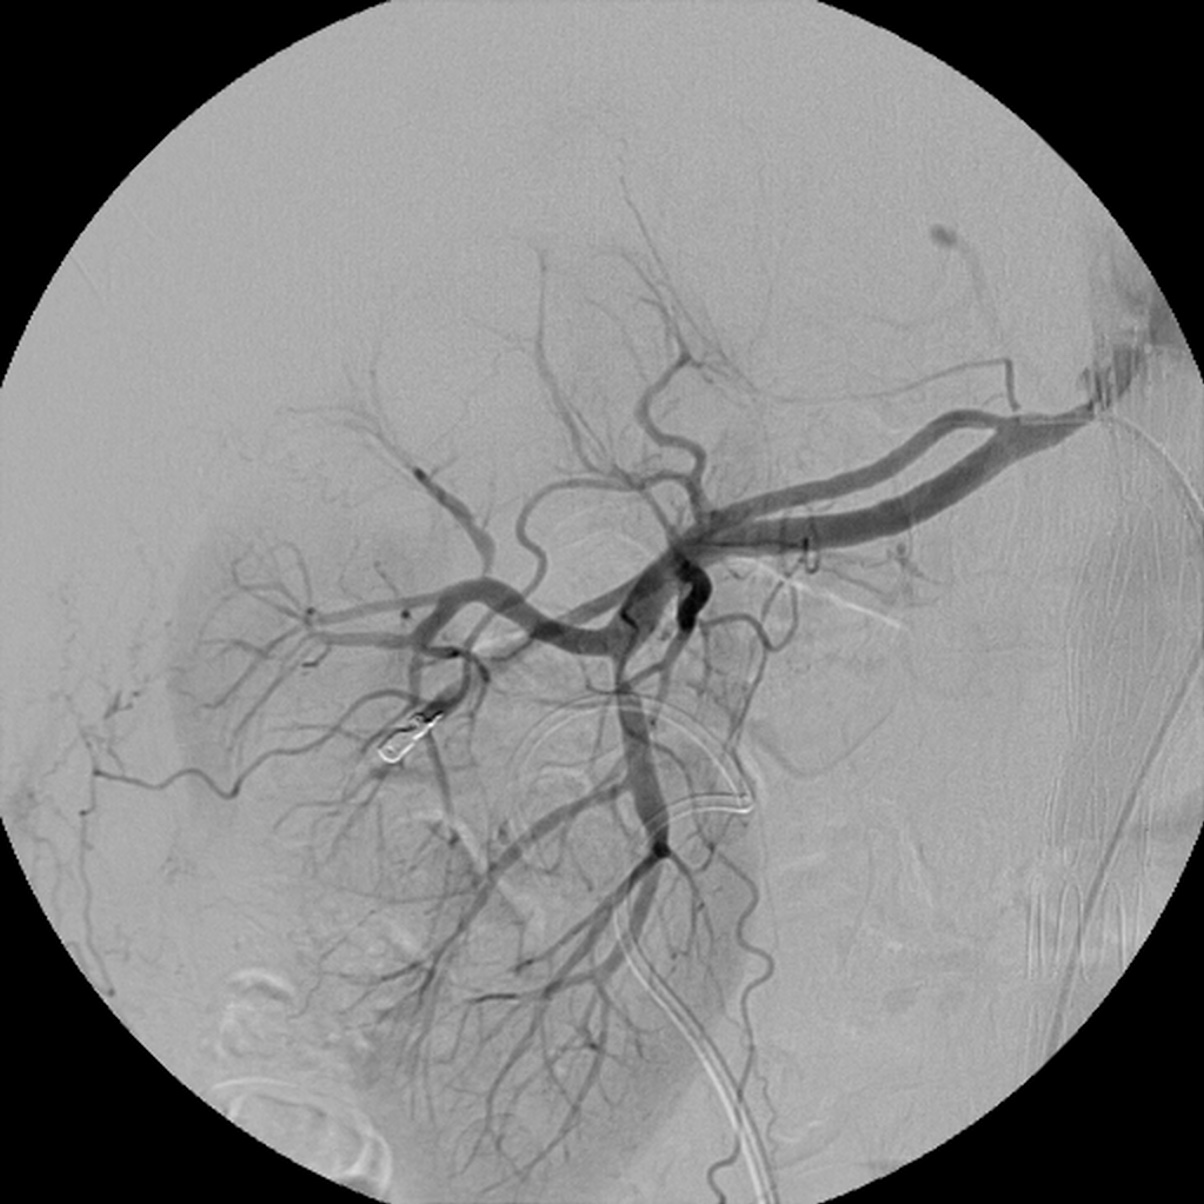

Хирургические процессы при эмболизации гемангиомы на фото

Раздел: Снимки-откровения